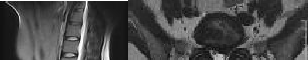

Preoperative MRI images are shown from a 67-year-old woman with neck pain, bilateral upper extremity paresthesias, progressively worsening balance, several falls, and increasing problems in both hands with dropping objects. Figure 1 is a sagittal view, Figure 2 is an axial cut at C2-3, Figure 3 is an axial cut at C5-6, and Figure 4 is an axial cut at C6-7. The patient’s motor strength is grade 4+ of 5 in the bilateral upper extremities.

What is the best next step?

4. Posterior decompression and fusion Discussion: D

The patient has degenerative changes with central and foraminal stenosis from C2-7, including spinal cord compression at C2-3, C5-6, and C6-7. Her progressively worsening balance, falls, and clumsiness are consistent with cervical spondylotic myelopathy. Given the progressive nature of the neurologic symptoms, surgery is recommended for patients with worsening

symptoms. Physical therapy potentially could provide pain relief but would not address the spinal cord compression. Cervical epidural steroid injection is not recommended because of the increased neurologic risk in the setting of substantial spinal cord compression. Given the multiple levels involved and the extension to the C2-3 level, an anterior approach would increase the risk of morbidity and pseudarthrosis compared with the posterior approach, which would allow adequate decompression of the central and foraminal stenosis.

Surgery for cervical myelopathy is performed to decompress the spinal cord, stabilize the spine, and prevent further neurologic injury. Most patients obtain considerable pain relief and some improvement in balance and clumsiness, depending on the severity of the symptoms. Complete resolution of all symptoms should not be expected.